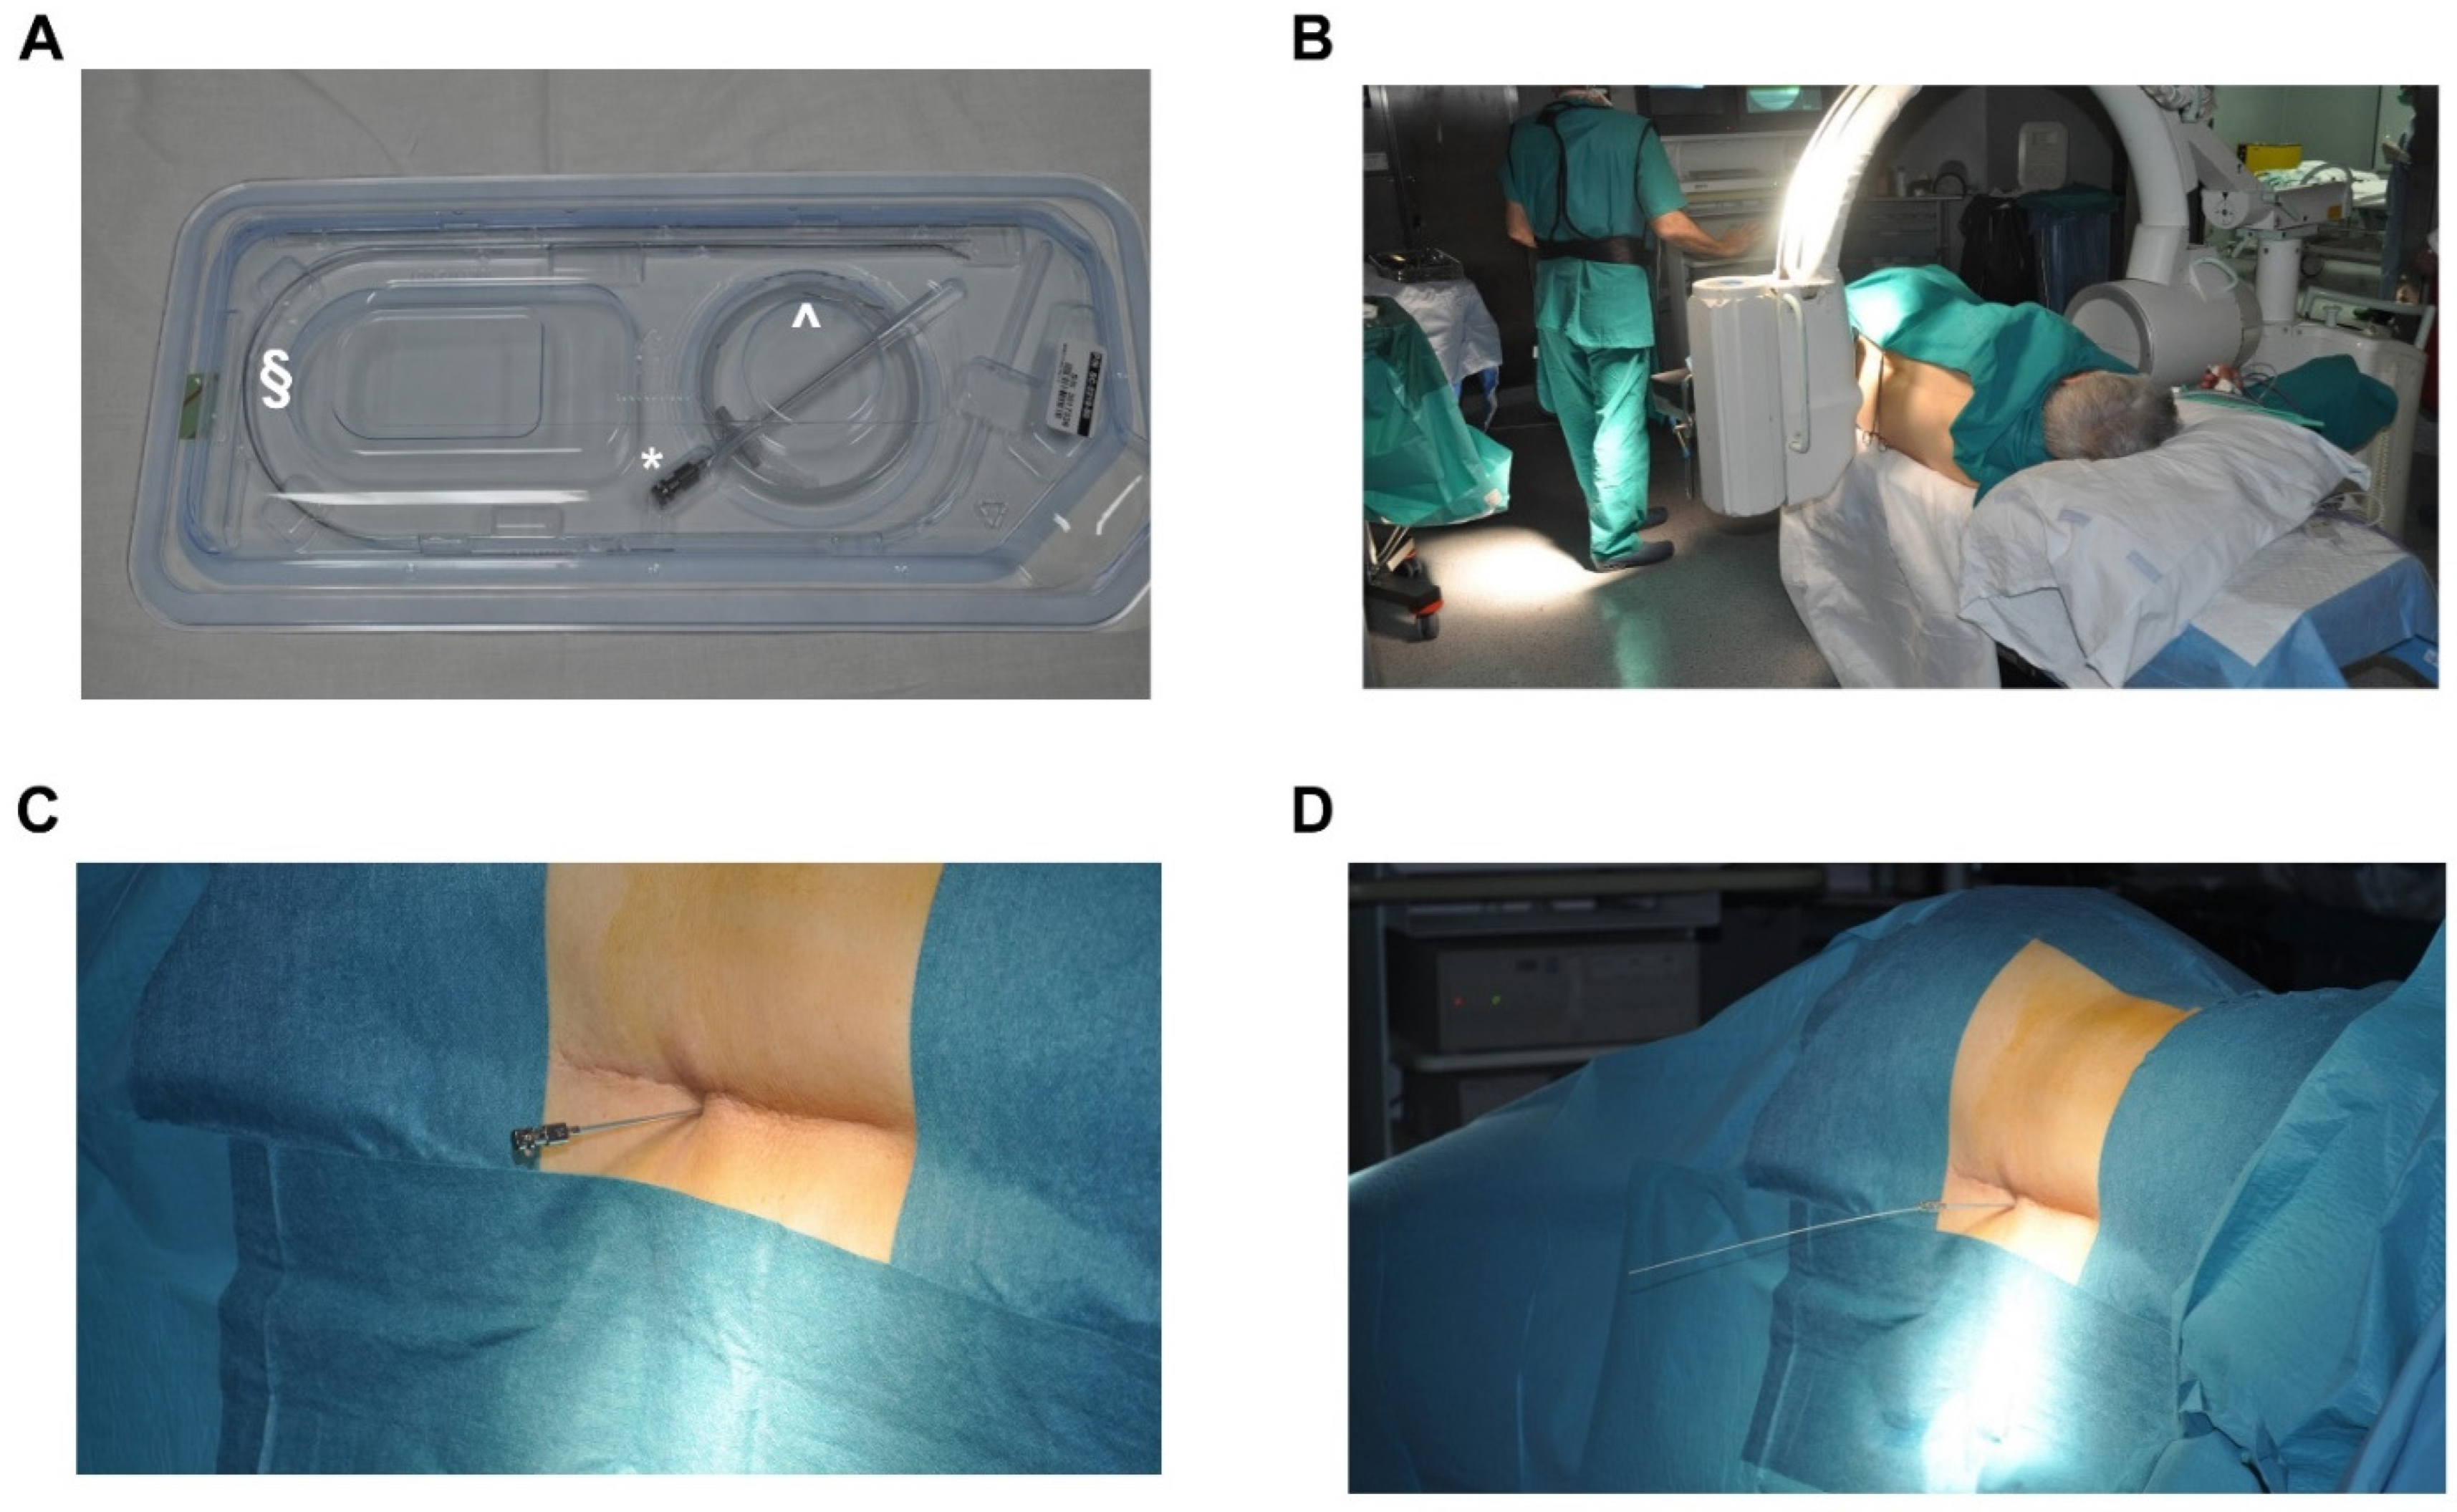

3.4. Procedure of Implantation